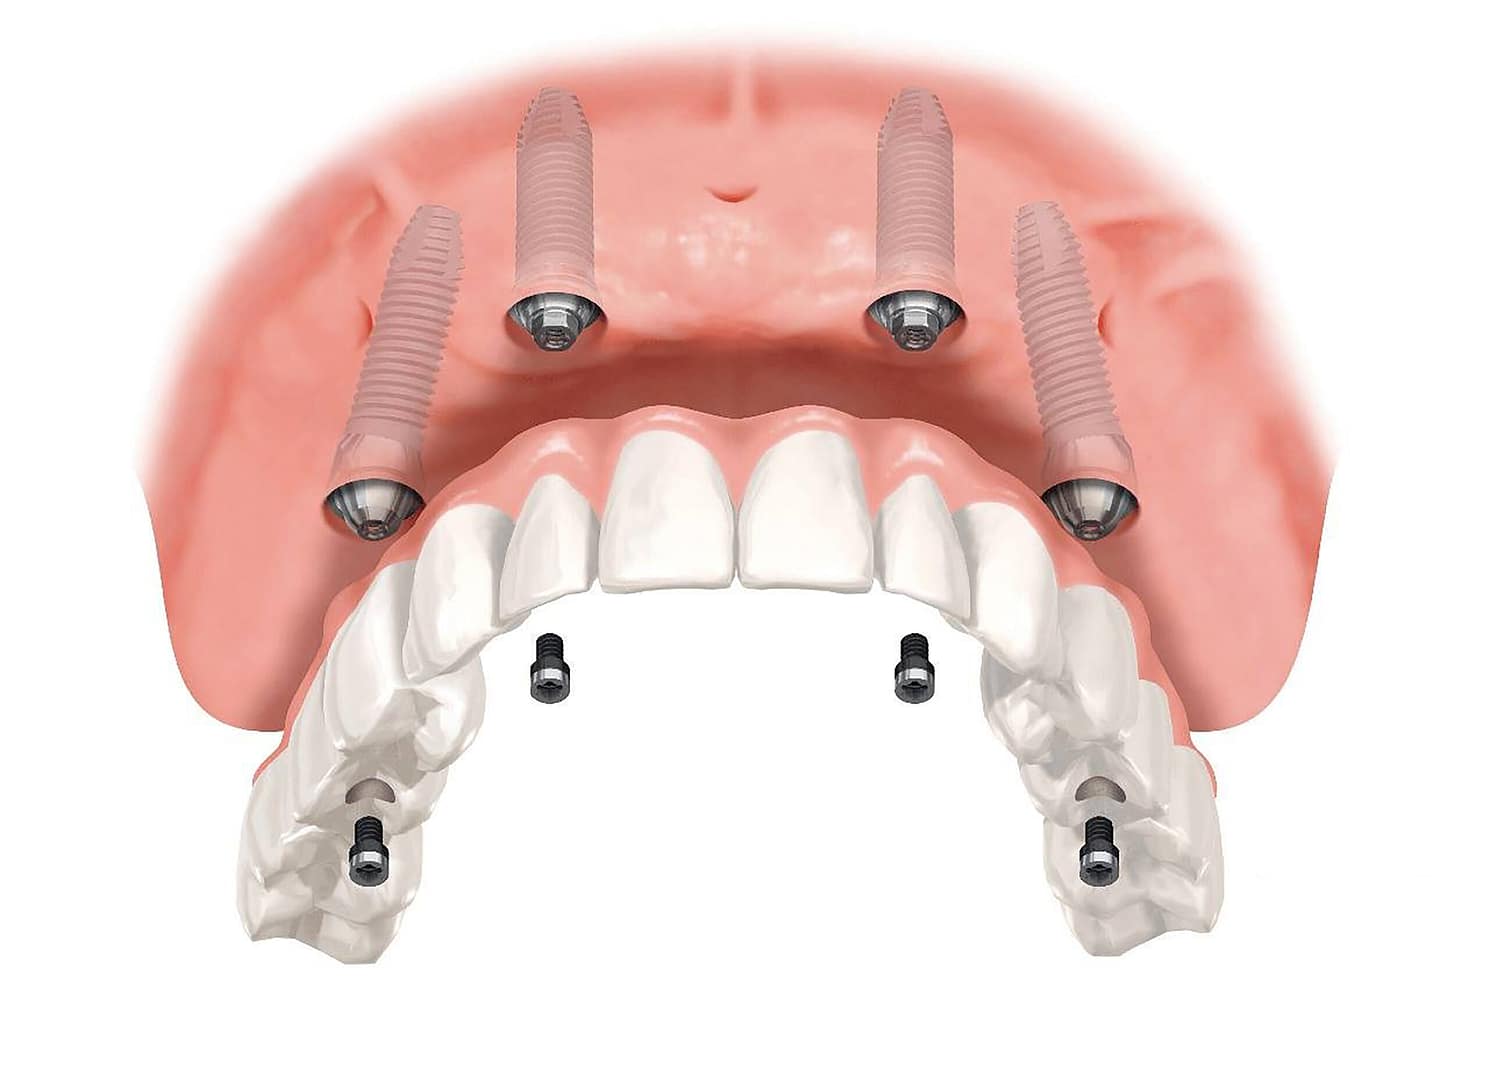

BlogEl Protocolo All-on-4®: Dientes Fijos y Función...

Leer másMi horrible experiencia con implantes dentales?